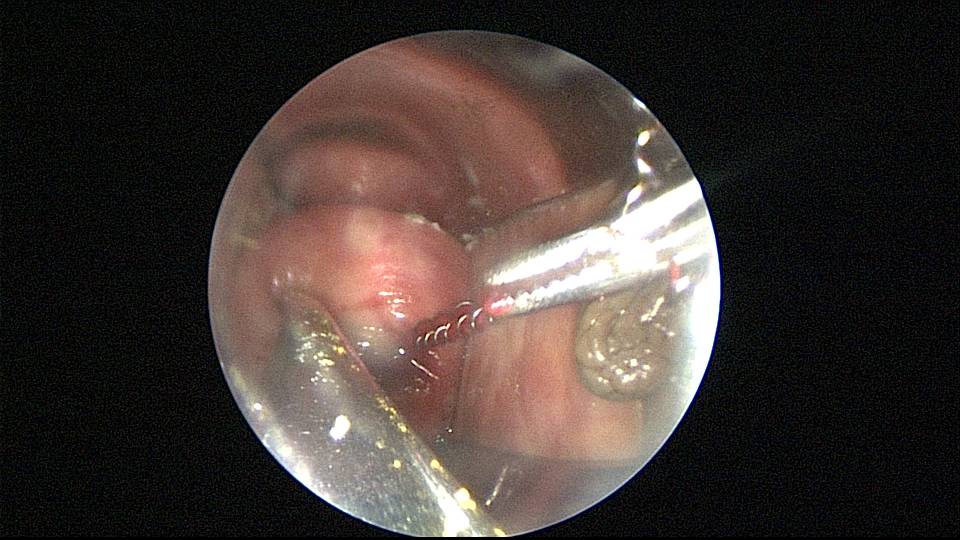

患者51岁,G4P3,顺产3次,闭经半年,外院B超提示有2个环。反复追问病史,还原宫内双环情况,24年前最后一次妊娠可能为带环受孕,行人流术,环未取出(医生和病人不知道有环),随即再次放环一枚。宫腔镜见母体乐环位置下移,纵臂卡在宫颈管内,宫腔镜难以进入宫腔,异物钳先取出母体乐。宫腔内见另一O型环,与右侧宫壁广泛嵌顿,异物钳、取环钩配合中弯钳拉出节育环,环完整,扭曲变形,宫壁见节育环割裂痕迹,宫腔无其他异常。